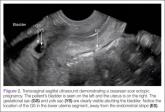

ArticleMy Most Unusual Case: Cesarean Scar Ectopic PregnancyAuthor:Deborah S. Kane, MDPublish date: October 1, 2014 Read More